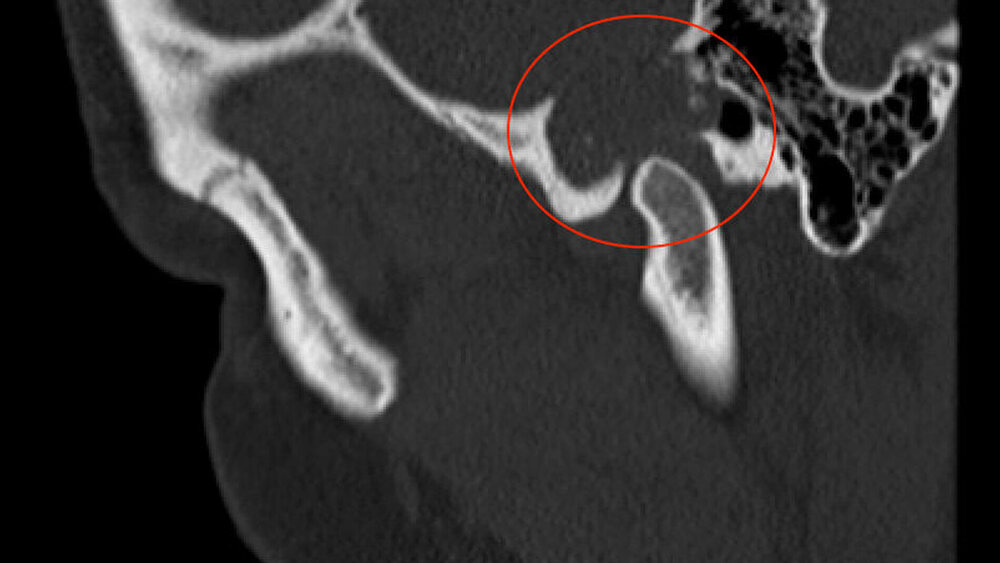

Zufallsbefund eines Riesenzelltumors bei langjähriger Bruxismus-Patientin